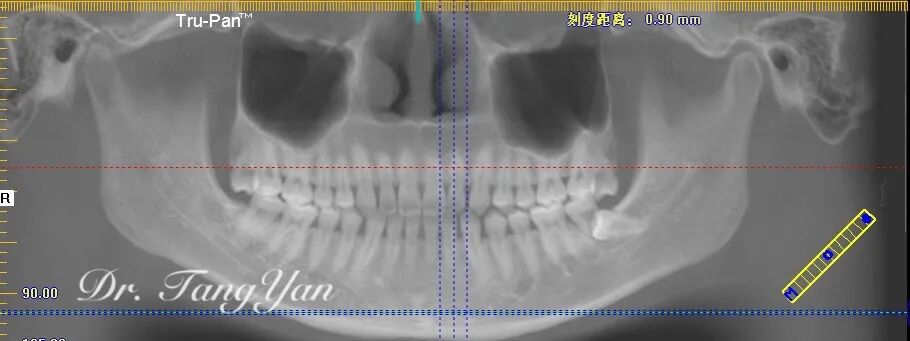

仅仅过了一年的时间,小7的牙根越来越少,小8依旧在向前生长,小7的地位要不保啦!